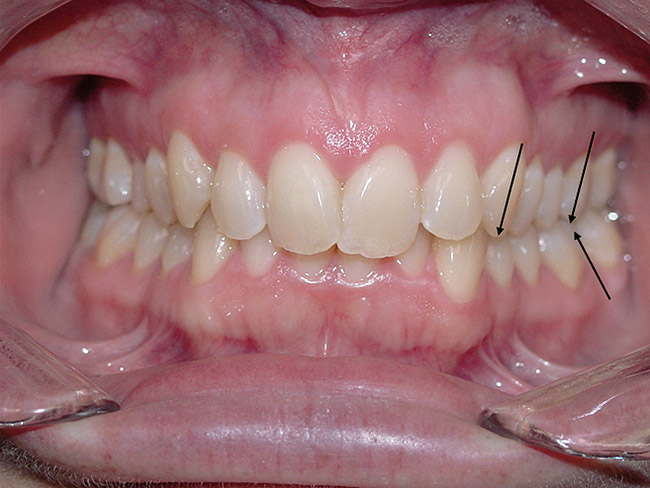

Figure 4  Palatally inclined upper central incisors  indicating a negative torque. In this situation the first  point of contact upon closure occurs in these teeth  leading (Occlusal Fence I) to a posterior shift and  distalization of the mandible.

Figure 4

Figure 5  After orthodontic correction, the upper  central incisors have a positive torque, and the posterior  shift of the mandible on closure is eliminated.

Figure 5

If the maxillary anterior teeth are positioned or inclined palatally, upon closure the lower teeth are going to first contact these teeth, which will force the mandible to shift to close into a retruded position. The objective is to try to identify this shift from primary contact to closure. This type of fence could potentially lead to shifting of the maxillary anterior teeth, breaking of the teeth, and/or muscular and jaw dysfunction as a result of posterior displacement of the mandible (Figure 2, Figure 3, Figure 4 and Figure 5).